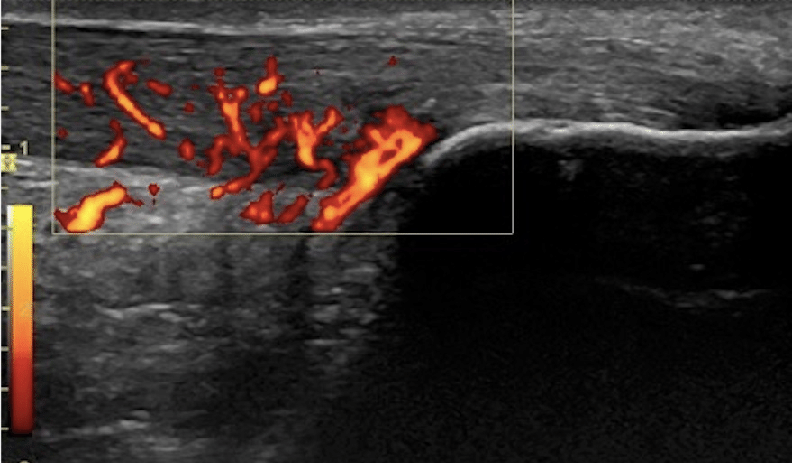

图:高定义多普勒下的血流增生

这张是纵向视图结合彩色多普勒血流的超声图:

大量异常血流(橘红色) 是慢性腱病的一个超声特征,特别是在中段型跟腱病中更明显。

它不等同于急性炎症的“经典炎症性充血”,但常提示慢性病变组织代谢活跃。

这直接决定:

这也是为什么指南强调:腱病治疗不能只看“疼不疼”,而要结合影像分型。